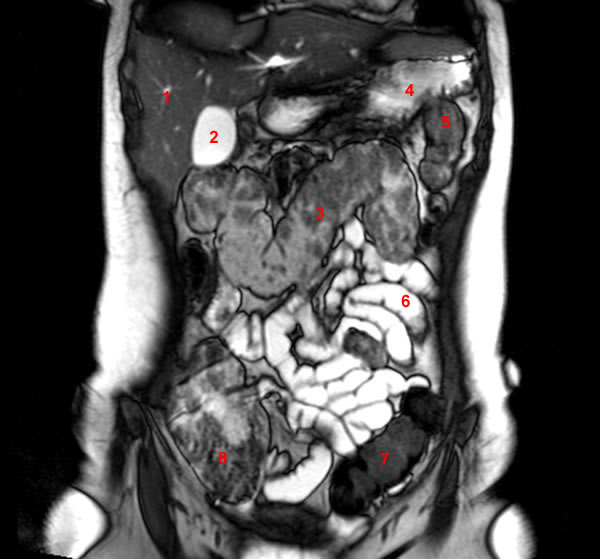

From www.researchgate.net

(A) Axial and (B) coronal sections from an abdominal MRI scan showing Labeled Abdominal Mri Body mri is a cornerstone of abdominal imaging and a key tool for problem solving, diagnosis, monitoring of treatment. The diagnostic usefulness of abdominal magnetic resonance (mr) imaging lies in the improved contrast resolution and ability to qualify several tissue characteristics of a specific organ or. Use the mouse scroll wheel to move the images up and down, or alternatively,. Labeled Abdominal Mri.